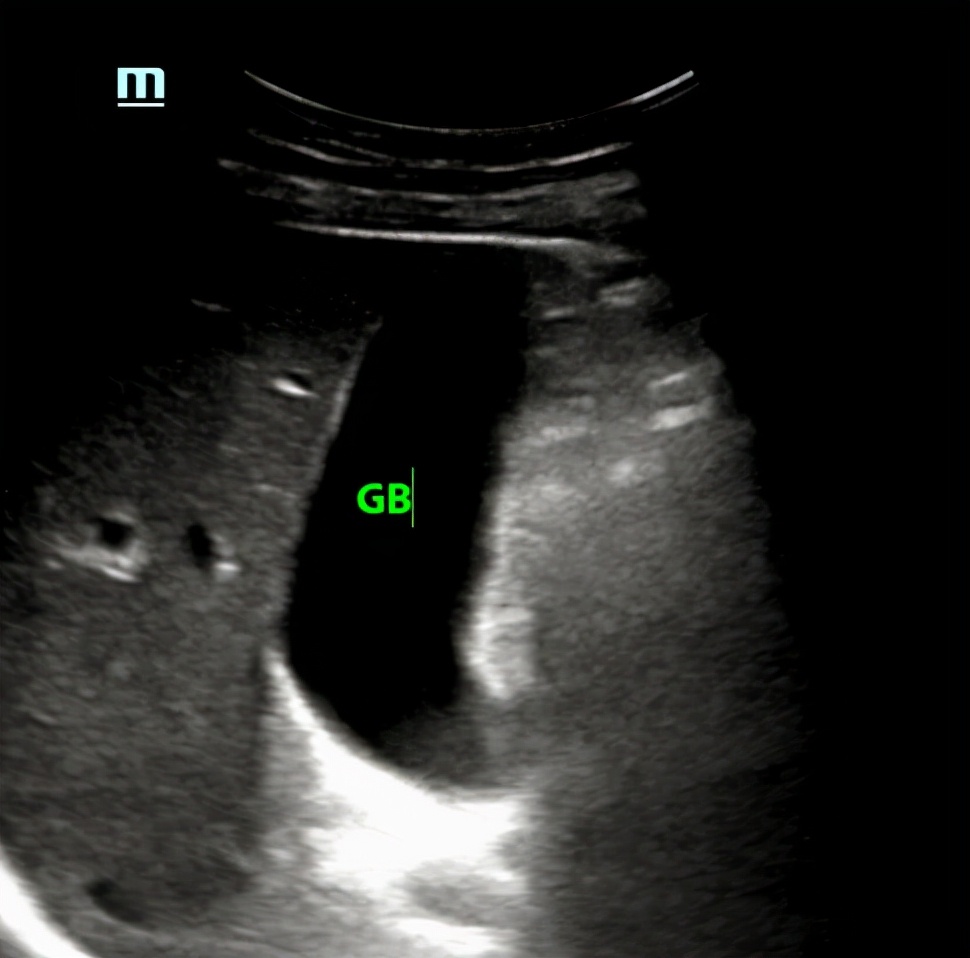

胆囊如图:

两年前的胆囊

从上图来看,胆囊内确实没有明显异常,只是形态看起来有些饱满,但胆囊颈部未能完全显示,肝外胆管也未能显示清楚。